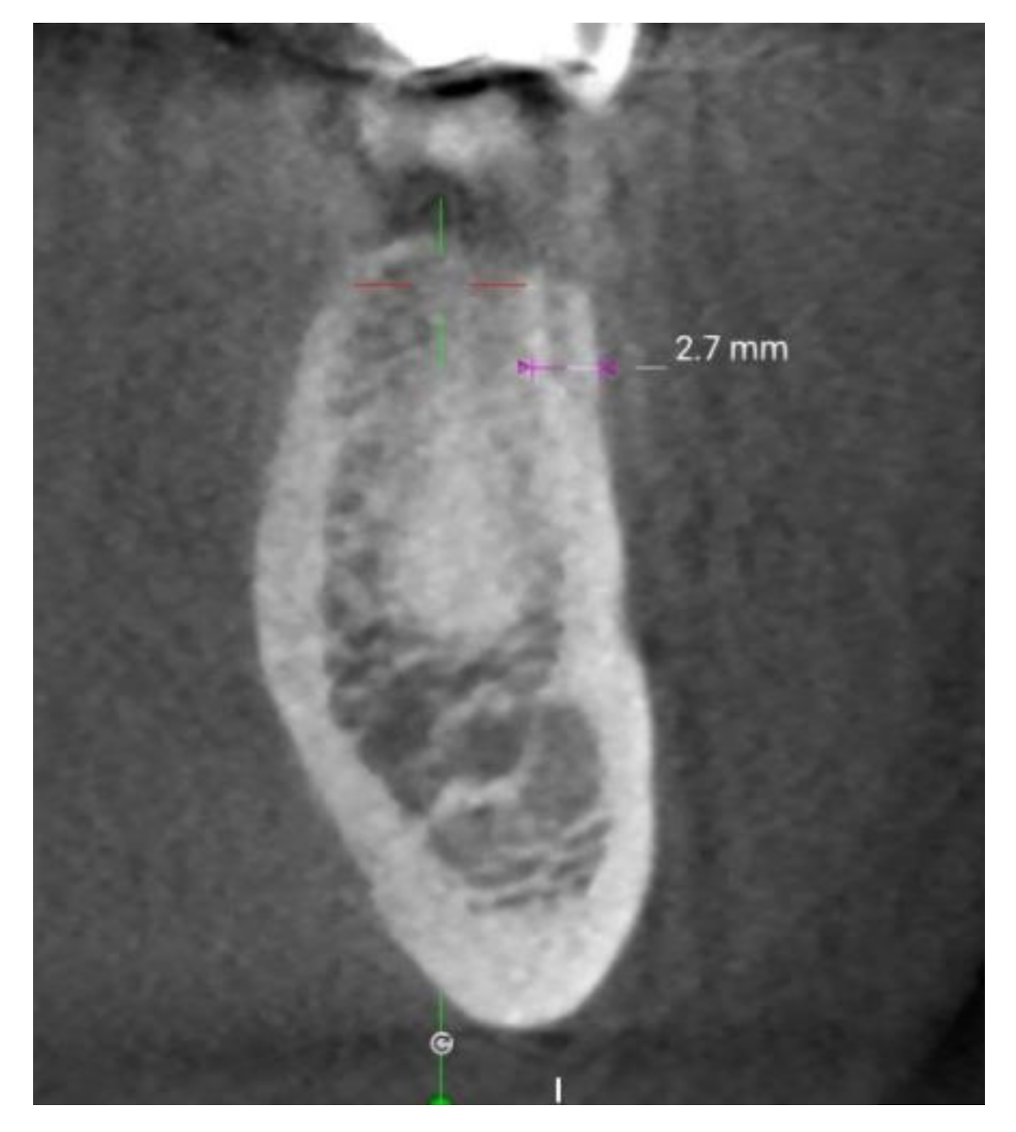

- Ko, Y.C.; Huang, H.L.; Shen, Y.W.; Cai, J.Y.; Fuh, L.J.; Hsu, J.T. Variations in crestal cortical bone thickness at dental implant sites in different regions of the jawbone. Clin. Implant Dent. Relat. Res. 2017, 19, 440–446. [Google Scholar] [CrossRef]

- Gupta, A.; Rathee, S.; Agarwal, J.; Pachar, R.B. Measurement of crestal cortical bone thickness at implant site: A cone beam computed tomography study. J. Contemp. Dent. Pract. 2017, 18, 785–789. [Google Scholar] [CrossRef]

- Ohiomoba, H.; Sonis, A.; Yansane, A.; Friedland, B. Quantitative evaluation of maxillary alveolar cortical bone thickness and density using computed tomography imaging. Am. J. Orthod. Dentofac. Orthop. 2017, 151, 82–91. [Google Scholar] [CrossRef]